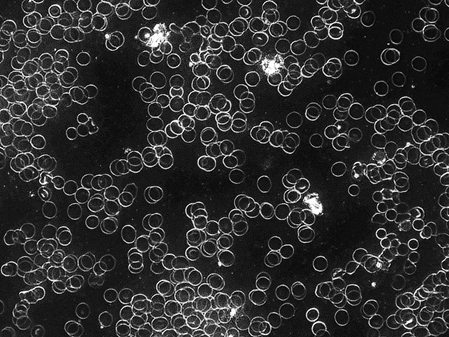

Blutbild vor dem Handy-Telefonat

Sehr gute bis gute Ausgangssituation – freischwimmende rote Blutkörperchen (Erythrozyten)

Freischwimmende rote Blutkörperchen haben eine gute Mobilität und sind gut funktionsfähig. Sie ermöglichen eine gute Durchblutung und sorgen für eine gute Sauerstoffversorgung.

Bei einzelnen Probanden war bereits vor dem ersten Telefonat eine leichte Geldrollenbildung erkennbar.